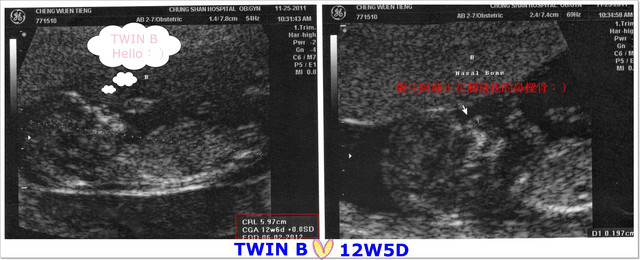

B寶寶身長:5.97公分(比一般值還大) 心跳:160/分

接著,就讓大家看看寶寶們吧:)

大約作了數十項的檢查之後,

才到了最後的重點-「頸部透明帶厚度檢驗」,

這個透明帶需要寶寶呈現自然平躺的姿勢才能測量得到哦!

寶貝們很乖的,很快的就讓醫生測量到,